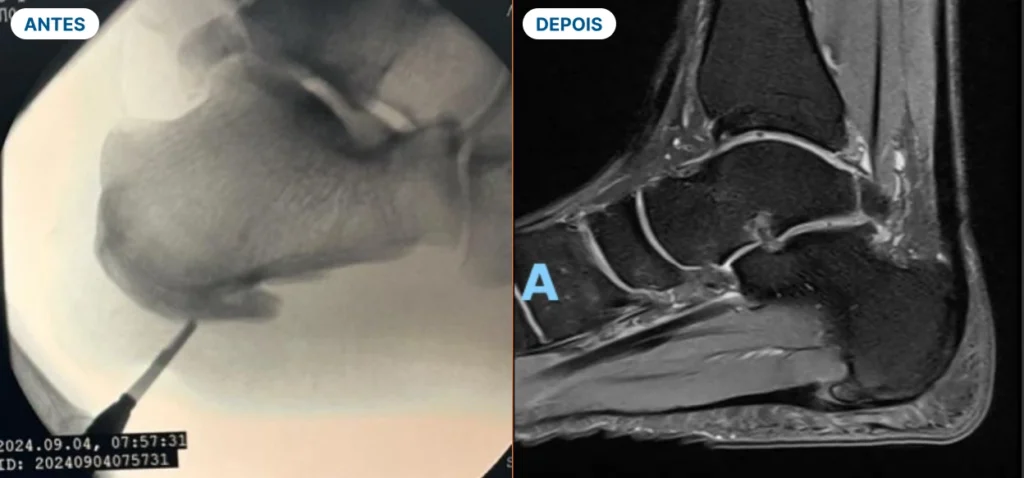

A Cirurgia Minimamente Invasiva e as técnicas regenerativas te permitem uma recuperação mais rápida e com menos dor

Com mais de 15 anos de experiência em cirurgias de pés e tornozelos, o Dr. Pedro Kanan trouxe para Santa Catarina as mais avançadas técnicas minimamente invasivas, permitindo que seus pacientes voltem a caminhar sem dor em menos tempo.

Técnicas minimamente invasivas, procedimentos regenerativos e recuperação mais rápida.